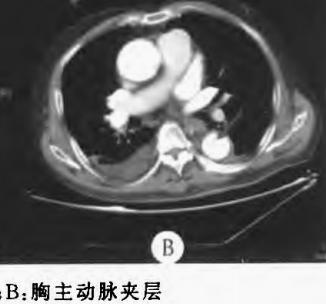

下面这个CT平扫,

这里有大问题!

很可惜,这个不是问题,很多CT平扫都有这种线样阴影!

下图是:大约肯定有血管内线样阴影!

下图是:隐隐约约不肯定有血管内线样阴影!